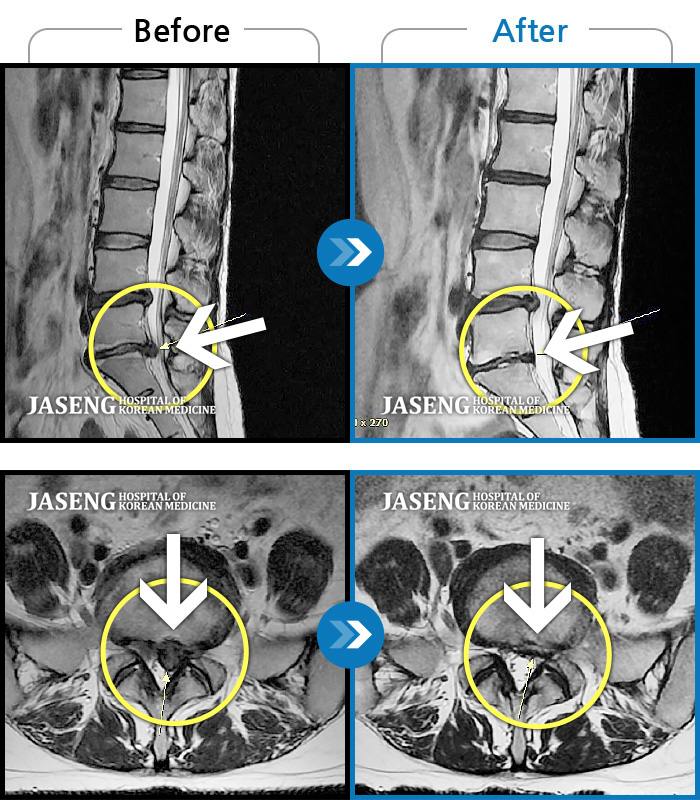

허리디스크

울산 · 정운석 원장

양측 하요추부 통증과 우측 하지 저림

촬영시기

2022.03.16 ~ 2022.11.12

2023.01.19